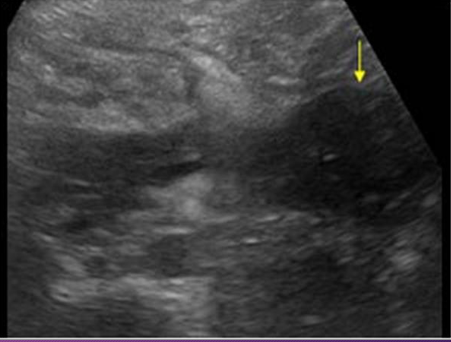

A _______ pancreatitis is an _______ process that spreads along _____ pathways, causing localized areas of diffuse inflammatory _____ of soft tissue that may proceed to necrosis and suppuration

phlegmonous; inflammatory; fascial; edema

______ pancreatitis occurs in ___-___ of patients with _____ pancreatitis

Phlegmonous; 18-20%; acute

Sonographically, phlegmonous tissue appears ______ in texture with good through-_____

hypoechoic; transmission

Sonographically, how does phlegmonous tissue appear?

Hypoechoic with good through transmission

Phlegmonous pancreatitis usually/commonly involves the ____ sac, ____ anterior _____ space, and transverse ______.